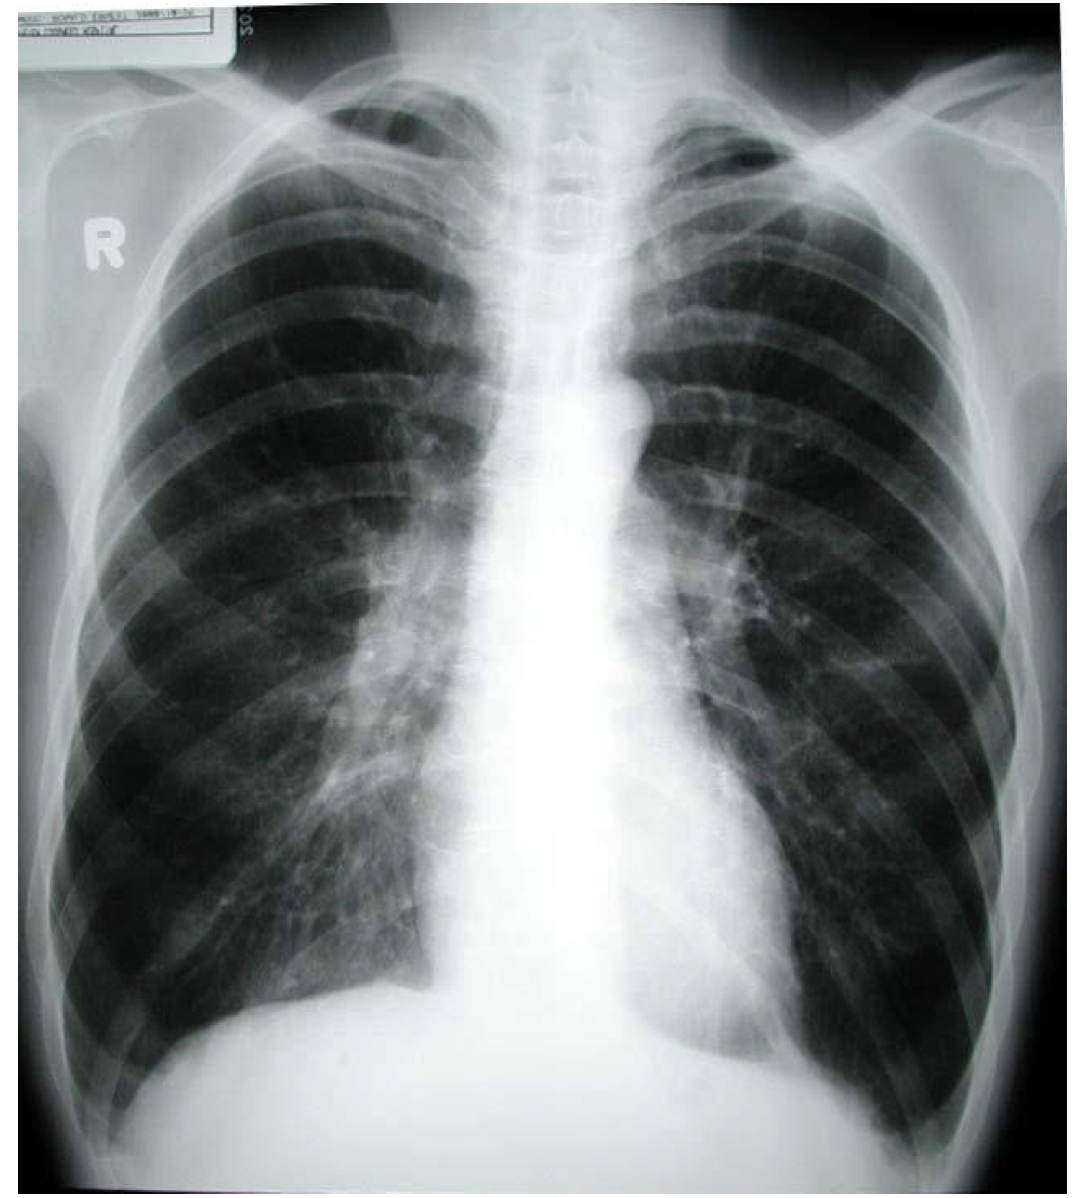

findings on chest X ray for COPD

– normal

– low flat diaphragms

– increased retrosternal airspace: check ribs anterior and posterior, and lateral xray

– low tapered heart shadow

– rapid tapering of the vessels with hyperlucency

of the lung – Usually characteristic changes on CXR in severe

COPD, 50% of the time in moderate COPD